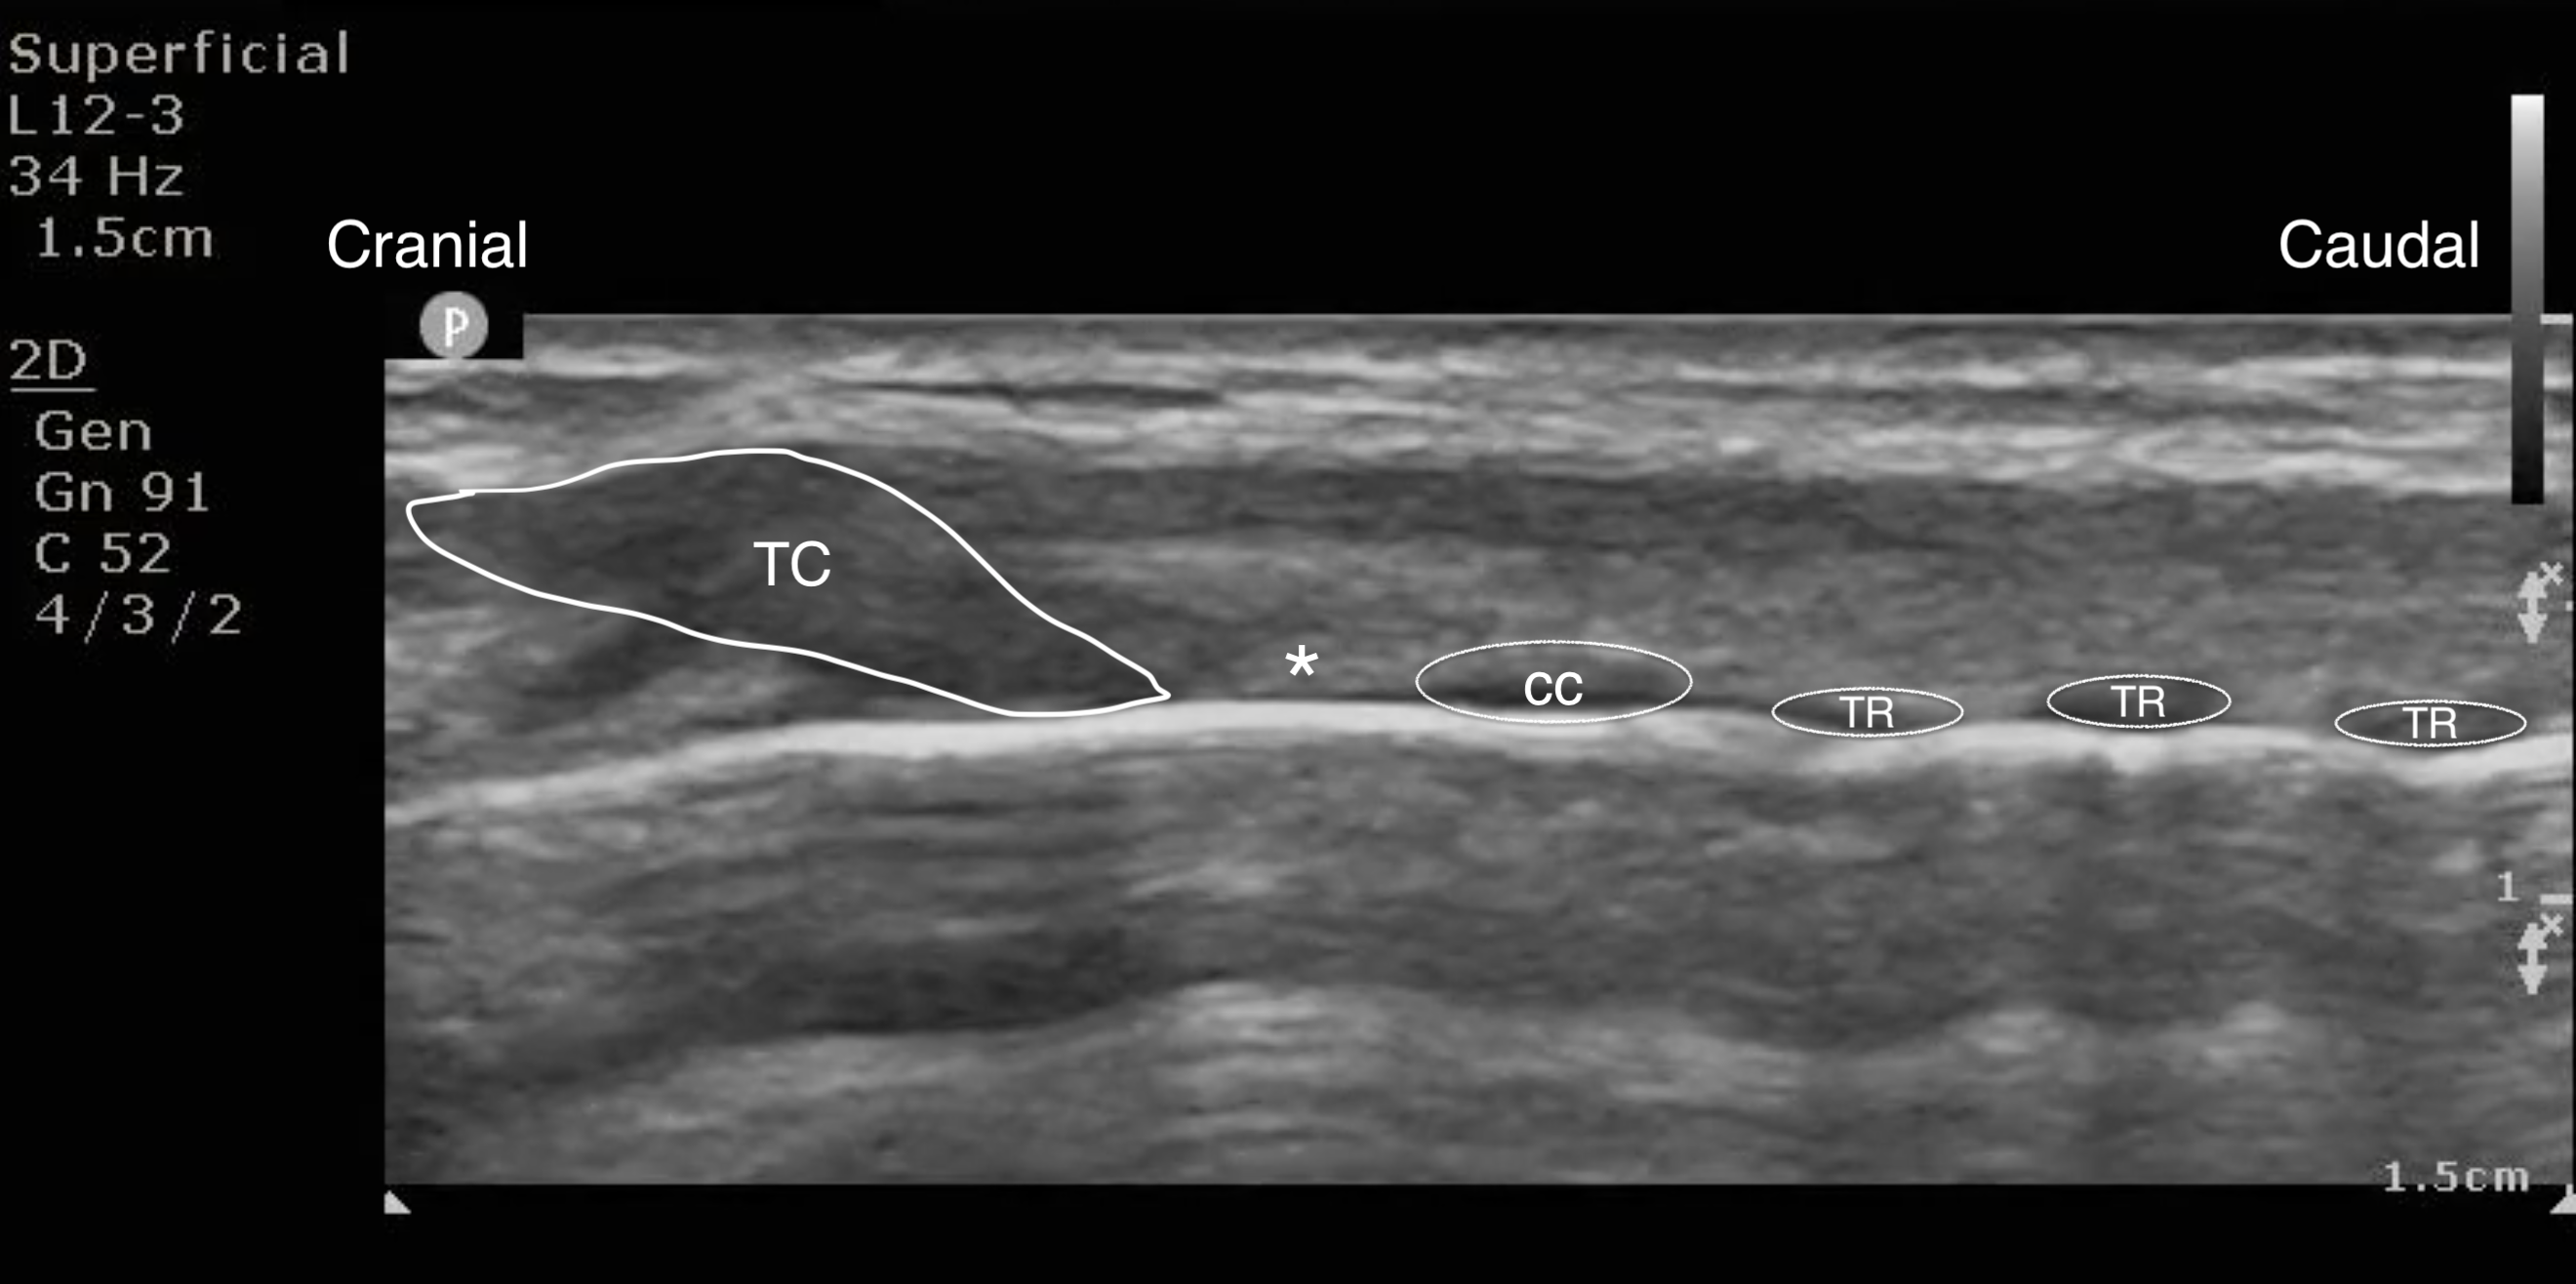

- Figure 10a and b. On the parasagittal view, from cranially to caudally, you see the thyroid cartilage (TC) followed by the cricothyroid membrane (*) then the cricoid cartilage (CC), and then tracheal rings (TR) which look like a “string of pearls.”